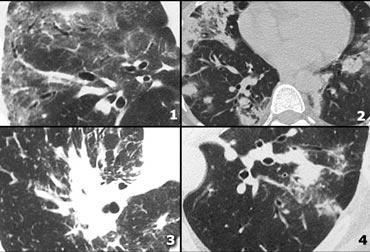

Phân bố quanh bạch mạch

Các nốt quanh bạch mạch thường gặp nhất trong sarcoidosis.

Chúng cũng xuất hiện trong bệnh bụi phổi silic, bệnh bụi phổi than và ung thư di căn đường bạch mạch.

Ca lâm sàng 1

Hình ảnh cho thấy một trường hợp điển hình của phân bố nốt quanh bạch mạch ở bệnh nhân sarcoidosis.

Lưu ý các nốt dọc theo khe liên thùy (mũi tên đỏ), gợi ý phân bố quanh bạch mạch.

Việc kiểm tra cẩn thận các nốt này ở vùng dưới màng phổi và dọc theo khe liên thùy là cần thiết, vì đây là dấu hiệu có độ đặc hiệu cao cho sarcoidosis.

Thông thường, sarcoidosis biểu hiện ưu thế ở thùy trên và vùng quanh rốn phổi, với phần lớn các nốt nằm dọc theo bó phế quản-mạch máu (mũi tên vàng).

Ca lâm sàng 2

Hình ảnh cho thấy một trường hợp điển hình khác của sarcoidosis.

Các nốt quanh bạch mạch (mũi tên) đi kèm với nhiều hạch bạch huyết phì đại (vòng tròn), đây là đặc điểm đặc trưng của bệnh.

Ở giai đoạn cuối của sarcoidosis, xơ hóa chủ yếu ảnh hưởng đến thùy trên và vùng quanh rốn phổi.